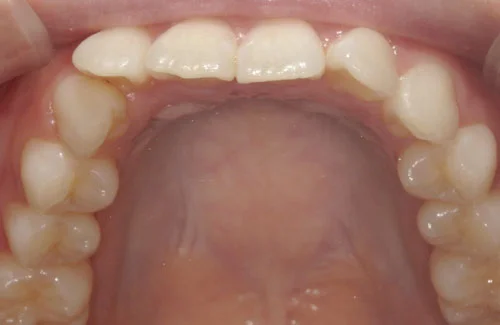

<症例7>歯がガタガタで噛み合わせが悪くお悩み

抜歯無し・マウスピースのみで矯正した症例です。

もともと歯列弓が非常に狭く、V字に近い形をしていたので噛み合わせも非常に不安定でした。

また、下顎前歯部がかなり上の方に生えていたため、下の前歯が上の前歯を突き上げてしまい出っ歯の状態になっていました。

現在では見た目はもちろん、臼歯の噛み合わせも改善しております。

患者様と症状

主訴:歯のガタガタ、噛み合わせが悪い

性別・年齢:20代女性

問題点:叢生(重度)、V字歯列弓、ディープバイト

診断:前歯部の叢生を伴うアングルⅠ級、骨格性Ⅰ級の不正咬合

主なリスク:臼歯の移動に伴い一時的に咬合しにくくなる、歯肉退縮

症状:叢生(そうせい) 過蓋咬合(かがいこうごう)

治療内容

治療期間:1年10ヶ月

治療費用:990,000円(税込)

プラン:Full2プラン

抜歯:無し

再診治療費:無し

追加治療費:無し

保定装置費:無し

治療前後の写真